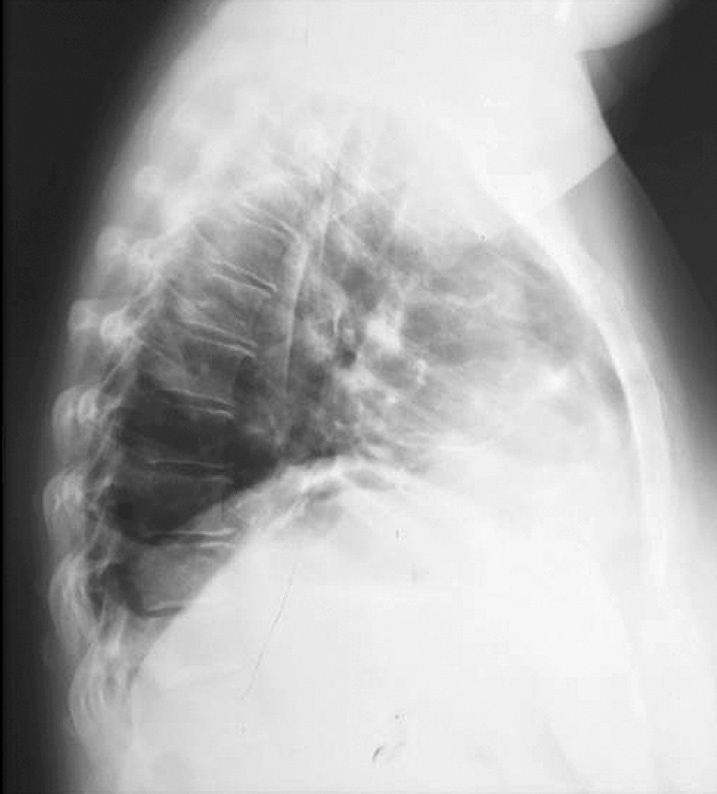

После вмешательства выполняли рентгенографию грудной клетки в прямой проекции (рис. 3). Установлен послеоперационный диагноз: «Лимфогранулематоз, массивное (bulky) опухолевое поражение средостения, IIХ стадия, состояние после оперативного лечения»; гистологический диагноз № 3308 от 04.06.04 г.: «Лимфогранулематоз, смешанно-клеточный вариант». Послеоперационный период протекал без осложнений. Пациентка выписана с выздоровлением на 15-е сутки с момента операции.

Рис. 3. Послеоперационная рентгенография грудной клетки в прямой проекции.

Fig. 3. Postoperative chest X-ray in direct projection.